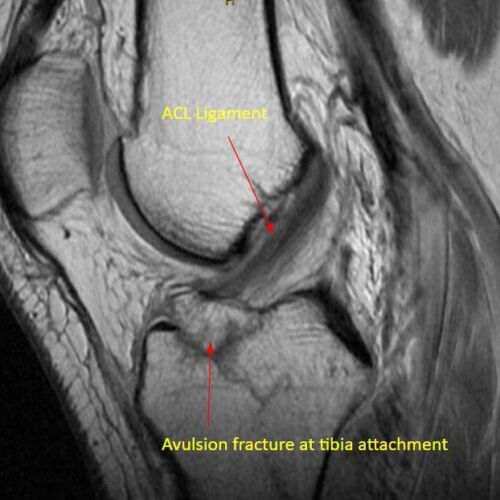

Dr. Pancio studied my daughters MRI before he came in and talked to us. He examined her knee and told us that her exam confirmed what he had found on the MRI which was missed by the radiologist. He prescribed the appropriate physical therapy and my daughter is on her way to making a full recovery without surgery! If she would have needed surgery, we have full confidence that Dr. Pancio would be great! He is very observant and knowledgeable. He explained everything that is going on with her knee also why and when it would hurt in different situations.